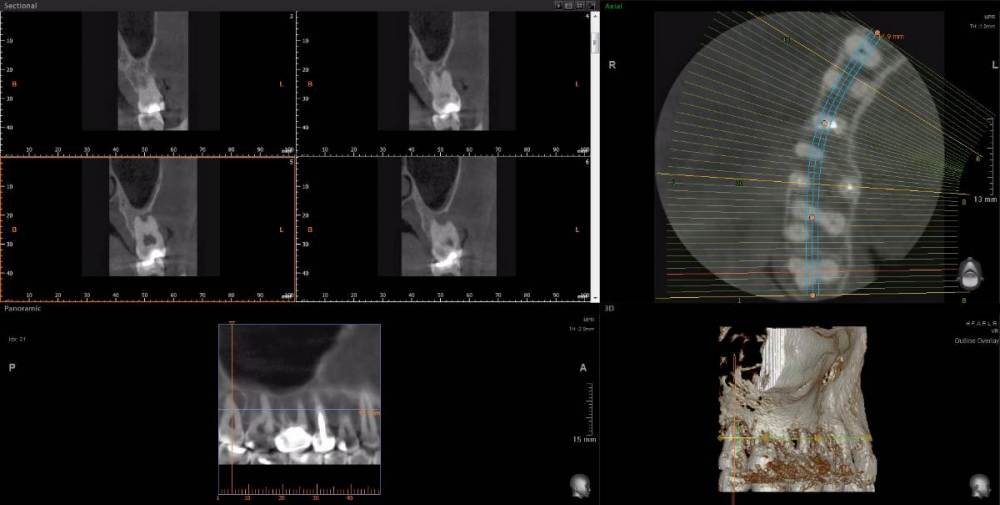

Рабин Опубликовано 18 мая, 2021 Автор Поделиться Опубликовано 18 мая, 2021 Добрый день! Сделала КТ этого зуба, как вы просили... https://cloud.mail.ru/stock/kkbze24nzBzfEqnUbdPwtsei Видите ли вы воспаление на нём и можно ли его спасти? Интересует также соседний 15 зуб. Спасибо! Ссылка на комментарий

wladdX Опубликовано 18 мая, 2021 Поделиться Опубликовано 18 мая, 2021 (изменено) Зуб 16, на мой взгляд, придётся удалить. Зуб 18 тоже Зуб 15 вроде бы и не вызывает особых восторгов, но и явного неприятия тоже. Изменено 18 мая, 2021 пользователем wladdX 2 Ссылка на комментарий

red_butler Опубликовано 20 мая, 2021 Поделиться Опубликовано 20 мая, 2021 18.05.2021 в 23:24, wladdX сказал: Зуб 16, на мой взгляд, придётся удалить. +1 Ссылка на комментарий

wladdX Опубликовано 29 мая, 2021 Поделиться Опубликовано 29 мая, 2021 18 - там приличных размеров корневая гранулёма, излечить нереально 1 Ссылка на комментарий